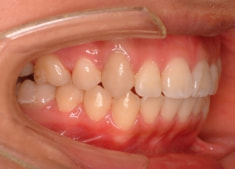

治療後(2年3ヶ月後)